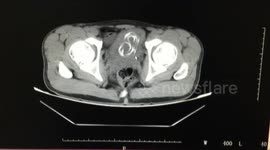

Turtle undergoes CT scan in Hebei, China

In a recent video shared by @NortheasternpeopleinBaoding on December 11, 2023, from Hebei province, China, a peculiar situation unfolded as the user's pet turtle underwent a CT scan at a local pet hospital. Concerned about the turtle's lack of energy and apparent sickness, the owner sought medical advice, leading to the recommendation of a CT scan. The video captures the unique moment when the turtle underwent the scan. Initially thought to be ailing, it was revealed to be pregnant during the scan.